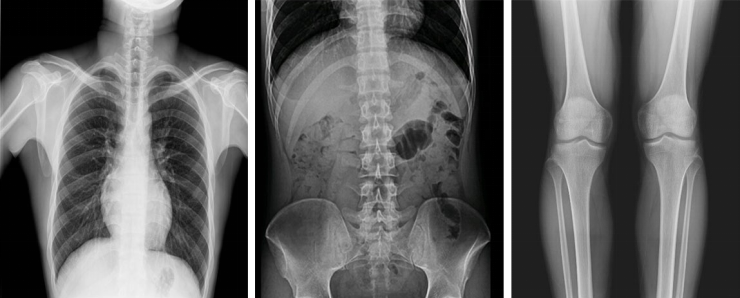

動(dòng)態(tài)DR影像采集幅面大,17×17英寸超大視野,可覆蓋成年人的全胸全腹,并且能在連續(xù)動(dòng)態(tài)中實(shí)時(shí)高清點(diǎn)片,還可以進(jìn)行視頻保存,在會(huì)診過程中可以回放影像檢查視頻,從而達(dá)到精準(zhǔn)診斷的目的。同時(shí)動(dòng)態(tài)DR還具有全身拼接功能,尤其適用于全脊柱和全下肢攝影,輔助脊柱畸形矯形治療、康復(fù)檢查,為臨床提供高精度圖像。